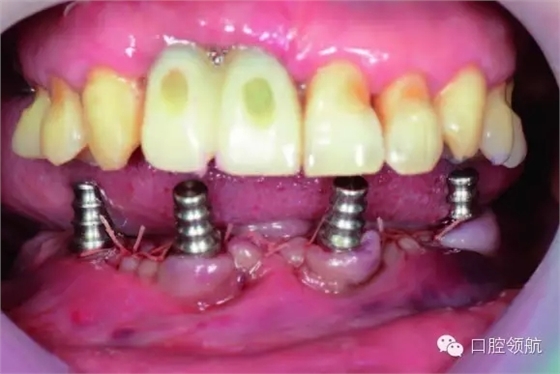

下頜為十數(shù)年前制作的三組金屬烤瓷橋修復(fù)體。右下4、5、7帶缺失的6;右下3、1及左下1、2帶缺失的右下2;左下3、4、5、8帶缺失的6、7,左下8修復(fù)后牙齒自然脫落,全景片無左下8的影像。幾乎所有的余留牙周圍的骨質(zhì)均吸收到根尖1/3。臨床上三組下頜金屬烤瓷橋均有較大幅度的松動(圖6-7,圖6-8)。

圖6-7 術(shù)前口內(nèi)照片

植入4顆NobelActive,后部為RP4.3*15,前部為RP4.3*13。安放閉口轉(zhuǎn)移桿(圖6-9,圖6-10)。